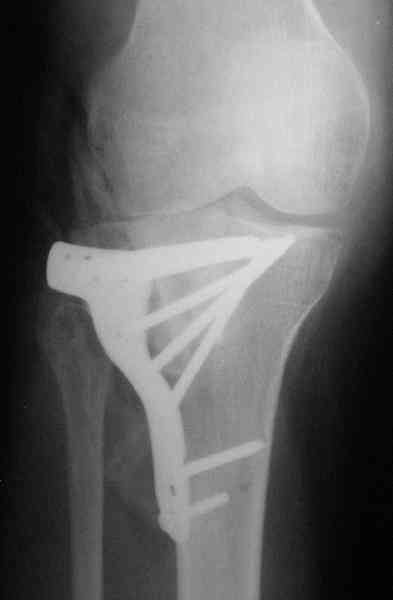

Re: Застарелый перелом 41С3

Уважаемый Абдурашид. Если нет противопоказаний , то из оперативных способов, я бы рекомендовал следующие: Полное замещение наружного мыщелка аллотрансплантатом либо открытая репозиция с элевацией и замещение дефекта ауто или аллокостью. В Ваших условиях , я бы рекомендовал второй способ. Во-время элевации необходимо разъединить фрагменты со стороны сустава ( надсечь скальпелем по линиям перелома, а затем тонким остеотомом их разъединить. При помощи долота произвести неполную остеотомию ( захватите не менее 1,5 - 2 см губчатой кости и поднять фрагменты, визуально отрепонировать и фиксировать 2-3 спицами. Дефект заместить костным ауто или аллатрансплантатом. Окончательная стабилизация пластиной ( лучше с угловой стабильностью, либо АВФ - позволит спокойно устранить угловую деформацию.

Недавно поступила больная через 1,5- 2 месяца.